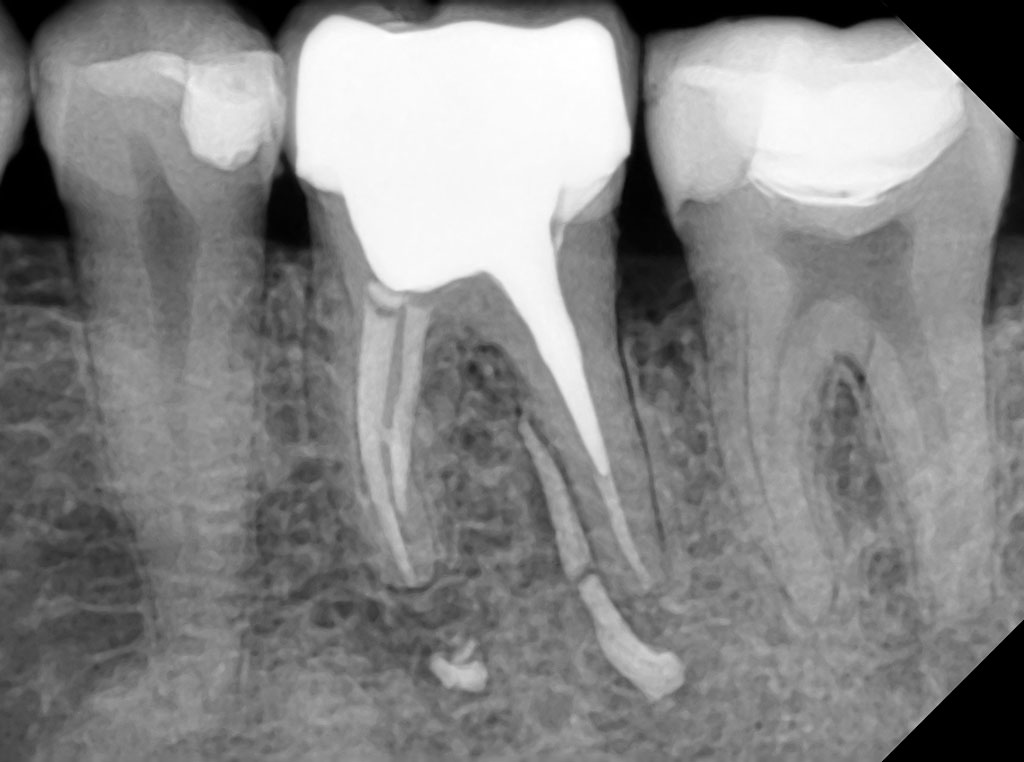

Сравнение качества снимков визиографов

Качество снимков зависит от множества критериев, приведенных выше. Давайте сравним снимки, полученные с визиографов различных производителей, по основным критериям: четкость, глубина, контрастность, детализация.

HDR-380 (HANDY)

unnamed.jpg

EzSensor HD (Vatech)

1rbbm0kxy9wewz8mug7fn4zrezg3xp01.jpg

Сравним снимки визиографа HDR-380 от HANDY и EzSensor HD от Vatech. Они практически идентичны, однако при внимательном изучении заметно, что снимок HDR-380 отличается большей резкостью, что облегчает врачу изучение деталей. При этом визиограф HANDY дешевле в 1,5 раза.

HDR-500 (HANDY)

unnamed (2).jpg

unnamed (3).jpg

Если сравнивать снимки визиографов HANDY HDR 500 и HDR 380, то заметно, что аппарат последнего поколения — 380-й — значительно выигрывает по глубине снимков и детализации. Такое качество достигнуто благодаря технологии CMOS. Это комплементарный металл-оксид-полупроводник, используемый в детекторе. Он снижает уровень шума при считывании изображения, повышает чувствительность датчика и скорость передачи изображения. Кроме того, CMOS отличается более низким энергопотреблением, по сравнению с аналоговыми технологиями.

Тем не менее качество снимков HDR 500 для диагностических целей врачи признают достаточно высоким, и модель является одной из самых востребованных, благодаря самой низкой цене на рынке.

afkt9xm1su9xc2f8wqmq2fg16oudeixo-(1).jpg

Portview GIX-1 (Genoray)

unnamed (5).jpg

Если сравнивать в этой же ценовой категории визиографы HDR-380 HANDY и Portview GIX-1 от южнокорейского производителя Genoray, то мы видим практически идентичное качество снимков, при этом HDR-380 выгоднее по цене.

unnamed (6).jpg

unnamed (7).jpg

SOPIX 2 (Acteon Group)

unnamed (8).jpg

Мы видим идентичное качество снимков, которое зачастую несколько уступает по четкости, контрастности и глубине моделям последнего поколения азиатских производителей - в частности HANDY.

Таким образом, можно сделать вывод, что китайский производитель Handy Medical Equipment значительно потеснил рынок европейских и южнокорейских производителей визиографов, а аппарат последнего поколения HDR-380 по качеству снимков не уступает более дорогим конкурентным аналогам. При этом HDR-500 того же производителя, сохраняя самую низкую цену на рынке в этой категории, обеспечивает оптимальное качество снимков, приемлемое для большинства стоматологических клиник.